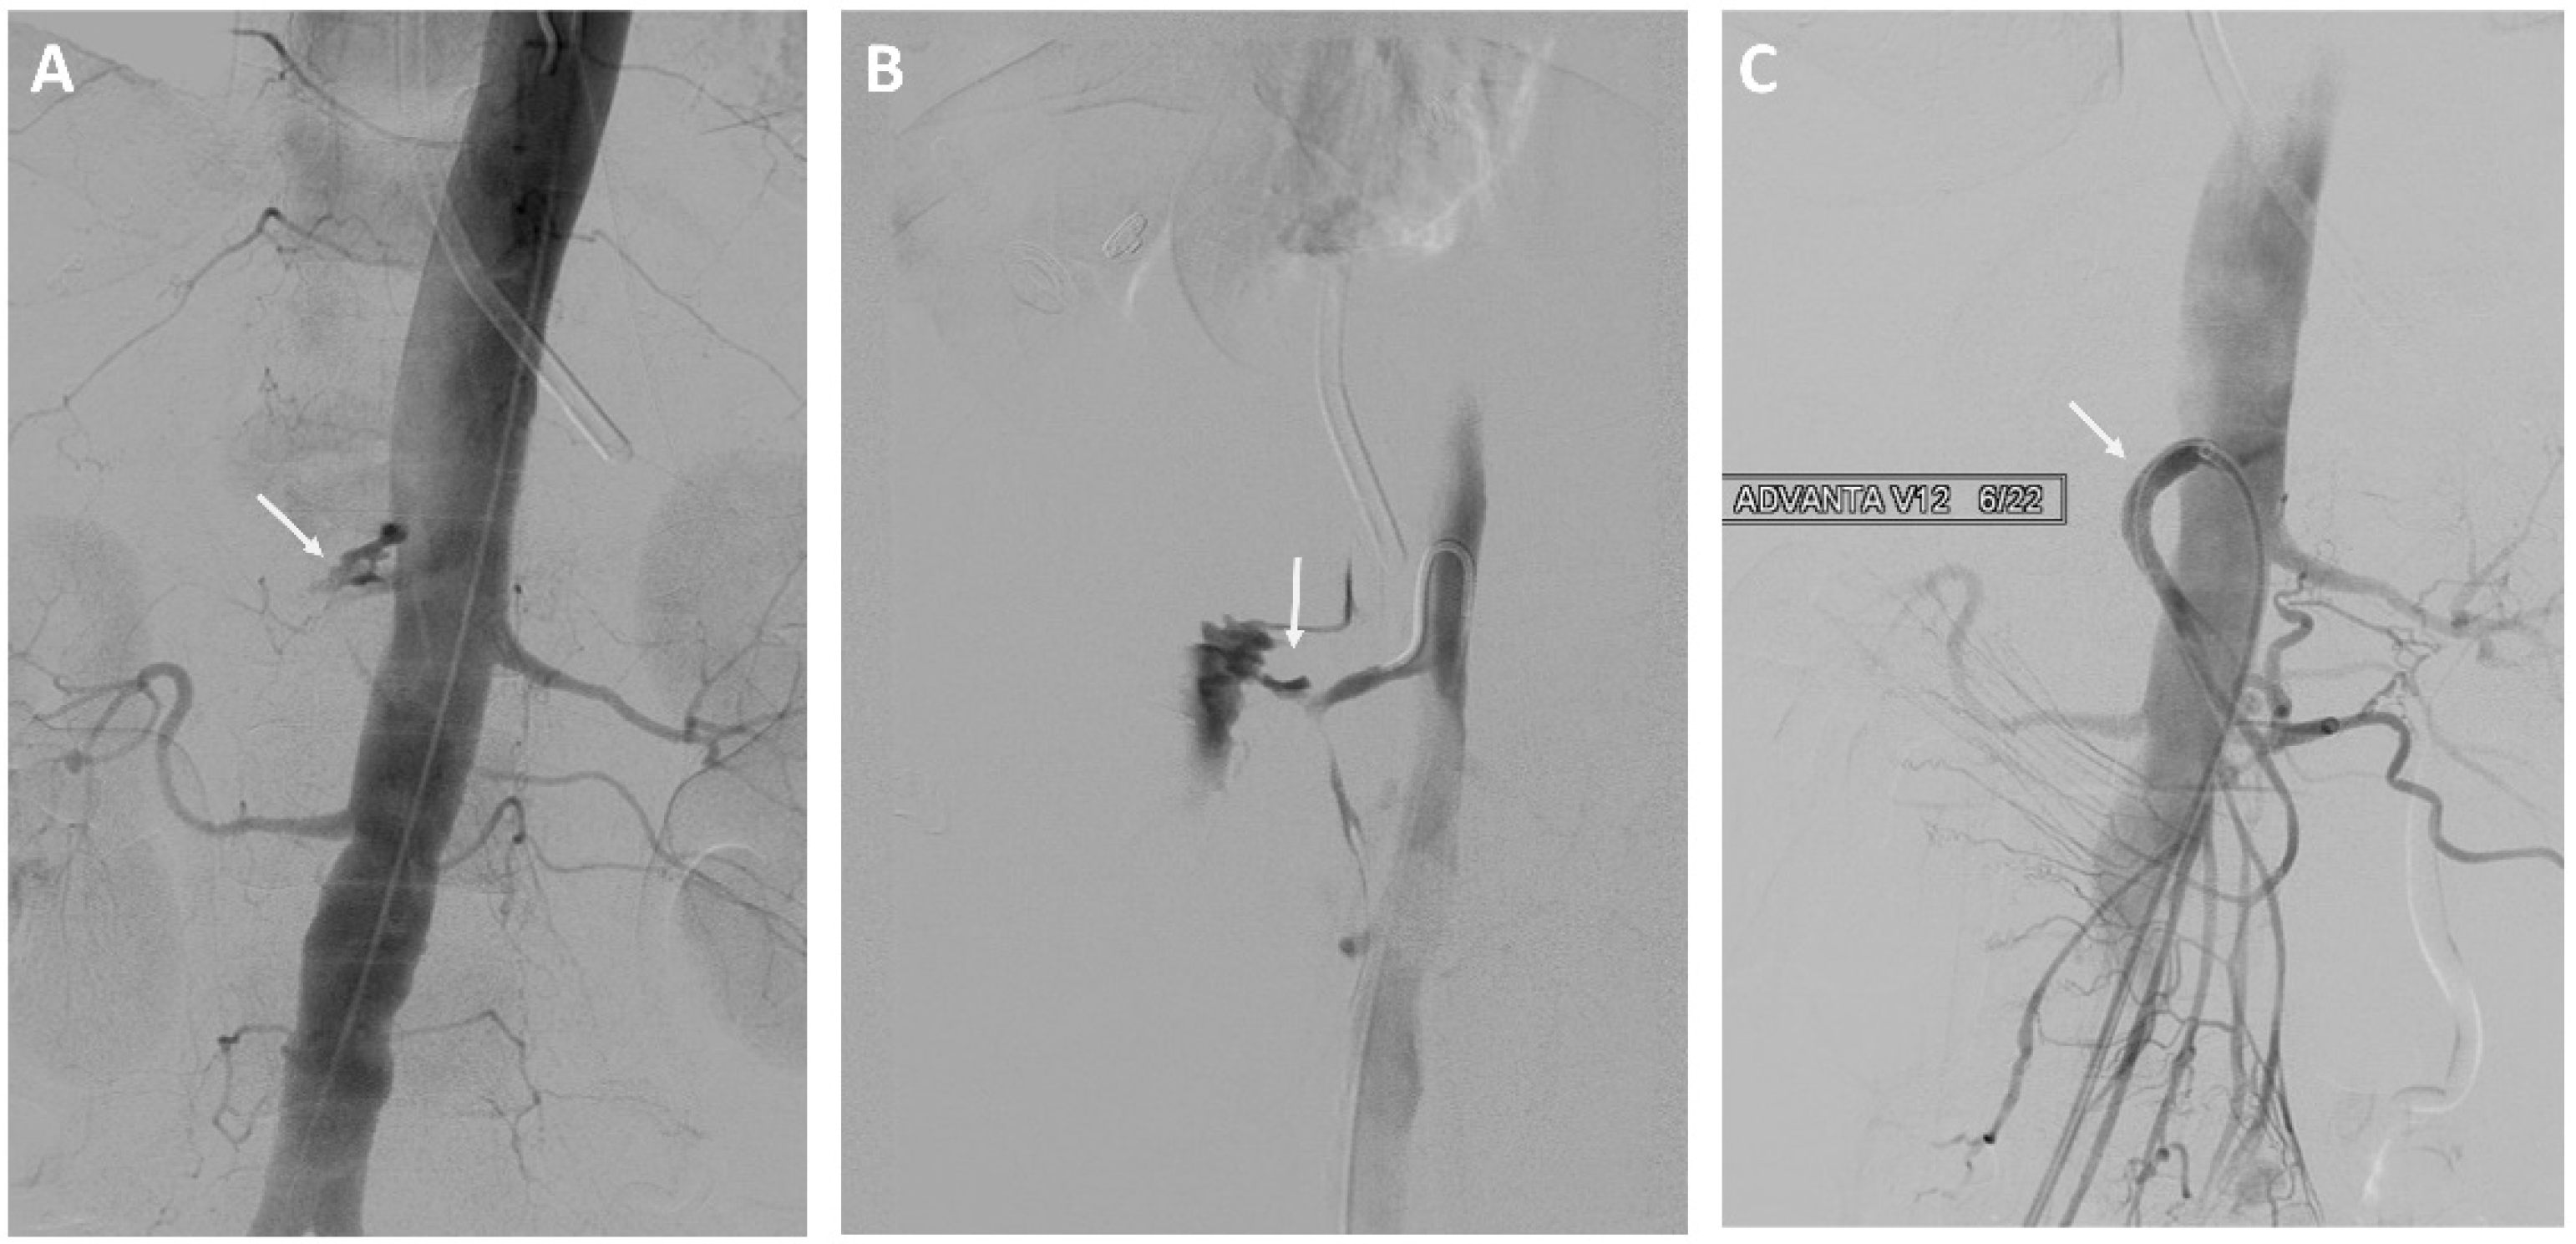

Eight of 37 (22%) patients in the EVT group underwent stent-graft treatment of the eroded vessels: celiac artery (n = 1), common hepatic artery (n = 4) see Figure 1, right hepatic artery (n = 1), and superior mesenteric artery (n = 2) see Figure 2. The stent-grafts used were Advanta V12TM (Getinge, Gothenburg, Sweden) in five patients, PK Papyrus covered stent (BIOTRONIK, Bulach, Switzerland) in one, covered balloon-expandable Jomed stent (Abbott Vascular, Santa Clara, CA, USA) in one, and polytetrafluoroethylene (PTFE)-covered Jostent GraftMaster® (Abbott Vascular, Santa Clara, CA, USA) in one. Technical success was achieved in all cases.

Figure 1.

A 61-year-old man with a history of pancreatic head adenocarcinoma and pylorus preserving pancreatoduodectomy (PPPD). (A) Angiography showing bleeding from the gastroduodenal artery stump and the hepatic artery. (B) Treatment of the hepatic artery with a stent-graft.

Figure 2.

A 73-year-old woman with a history of intraductal papillary mucinous cancer of the pancreatic head and pylorus preserving pancreatoduodectomy (PPPD). (A,B) Angiography showing bleeding from the superior mesenteric artery. (C) Treatment of the superior mesenteric artery with a stent-graft.